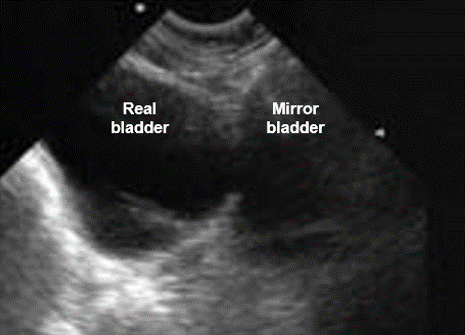

Mirror Image

And finally, the mirror image is formed near a very reflective interface; it is observed mainly at the diaphragm. The ultrasound is reflected on the diaphragm towards the liver tissue and then they follow the opposite way. The ultrasound machine ignores this reflection and considers it as a rectilinear movement of the ultrasound.